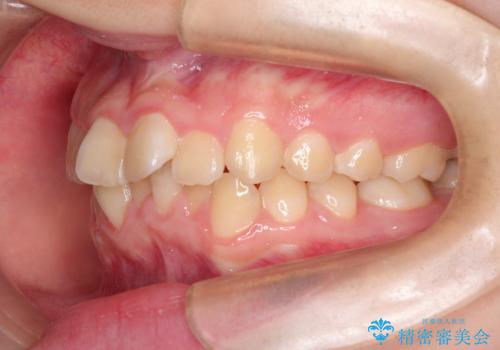

上下の前歯のガタガタを目立たず治したい インビザラインによる見えない矯正

- 上下の前歯のガタガタを治したいとのことで来院されました。

お友達がインビザラインによるマウスピース矯正を行っているとのことで、マウスピースでの治療を希望されました。

上下の歯と歯の間をわずかに削り、並べる計画としました。